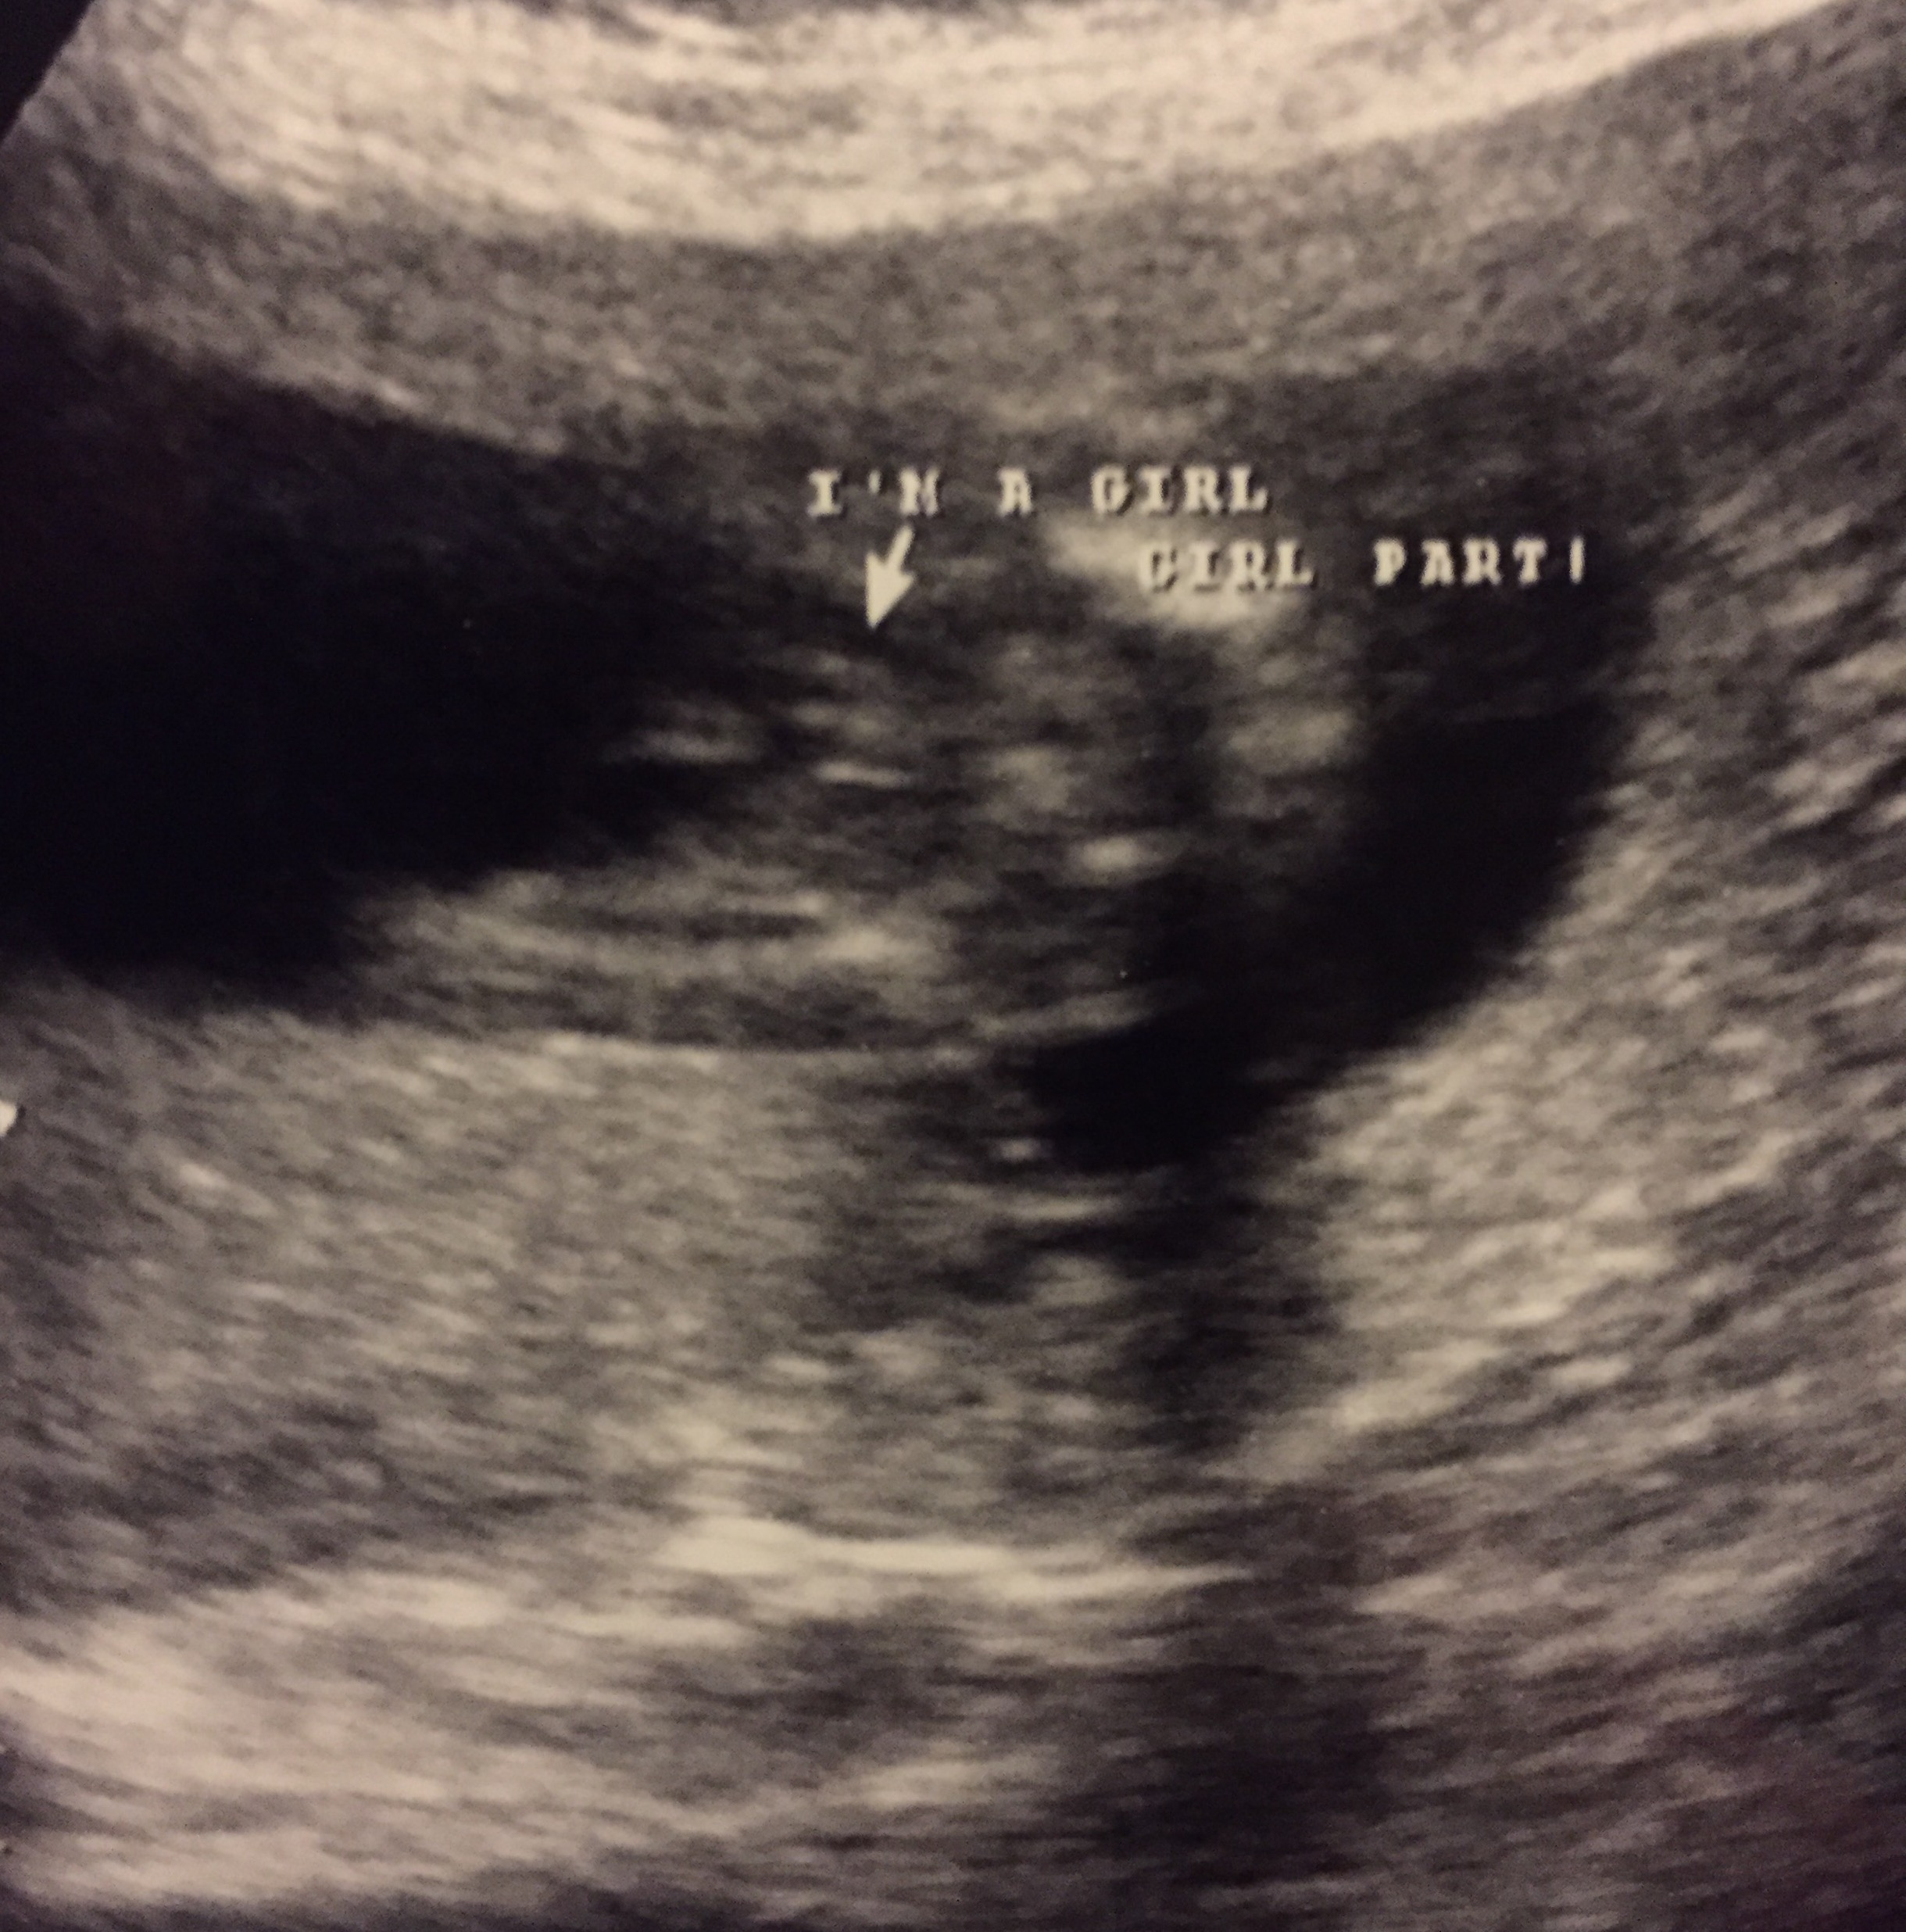

I had an elective ultrasound done and the cord was between the baby's legs the whole time. Can I get your opinions on whether this looks like cord or girly bits, please? I have boys and I'm praying this is a little princess, but I don't want to get my hopes up just yet. Attachment 29033Attachment 29034